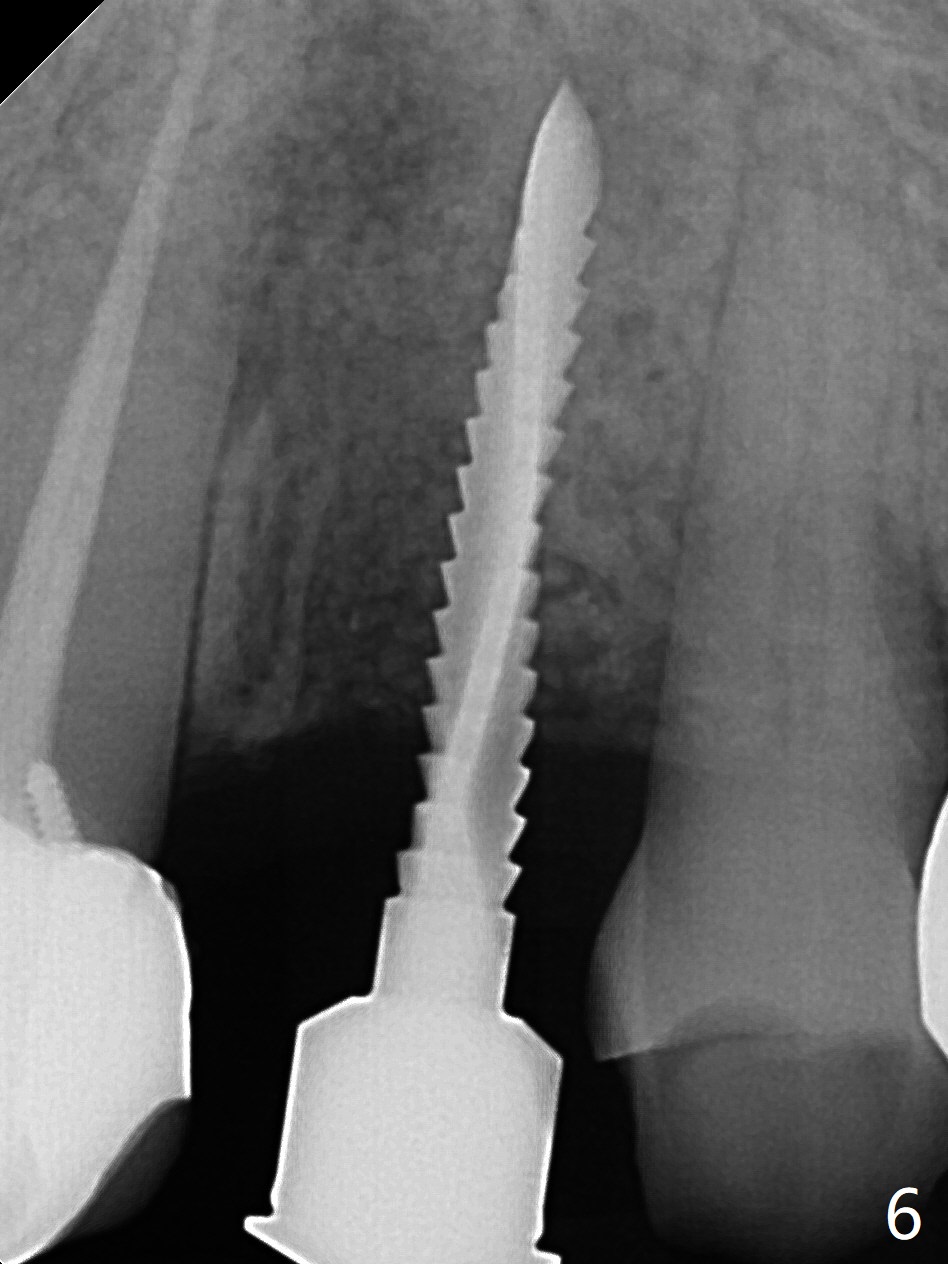

植骨后6个月牙槽窝愈合正常,角化龈和牙槽嵴都宽(图一),导板种植好像不需要切口。利用导板植入,但是离尖牙牙根很近(图二,三)。取出植体后,准备切开改变钻洞方向(图四,五),结果效果不错(图六,七),腭侧骨壁低,安置愈合基台,植骨(图八:*),覆盖胎盘膜,缝合。